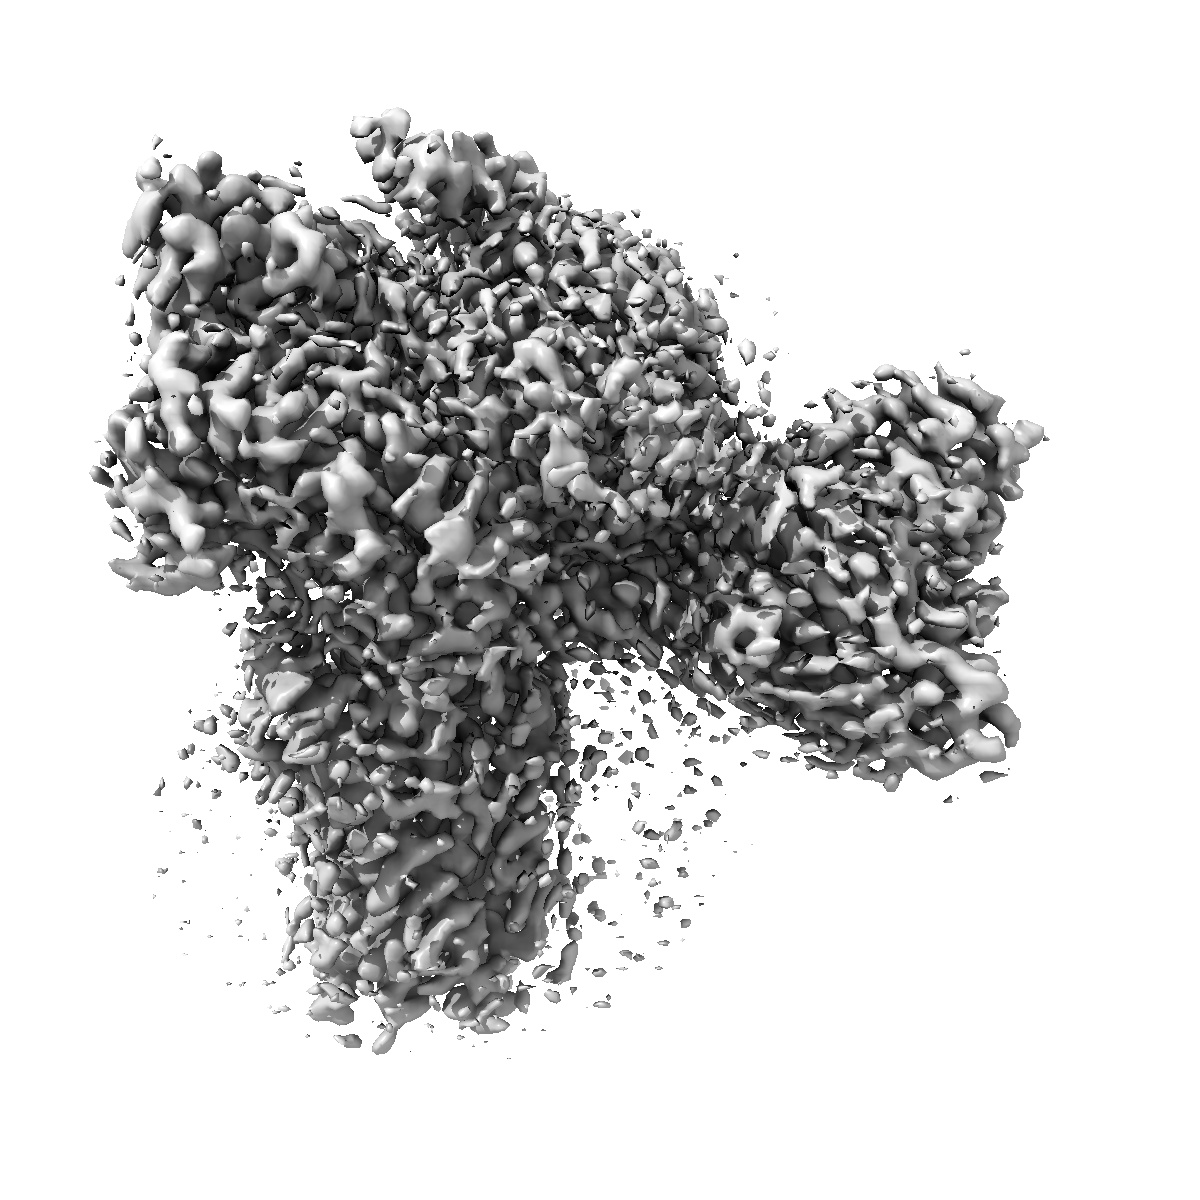

Cryo-EM structure of the anamorelin-bound ghrelin receptor and Gq complex

Single-particle2.9 Å

Sample: Anamorelin-bound ghrelin receptor in complex with Gq